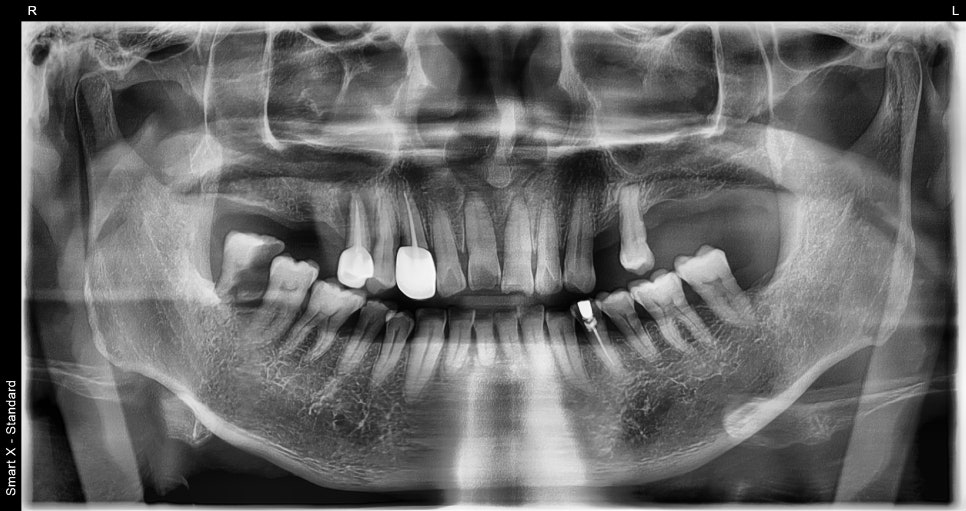

초진 시 촬영한 전체 파노라마 X-ray 사진

정밀 진단 중, 앞니 외상 외에도 오른쪽 어금니 쪽에 진행된 충치와 골 손실이 확인되었습니다.

결국 해당 부위는 발치가 필요했고, 뼈이식과 함께 임플란트 수술이 시작되었습니다.

이 시점부터는 단순한 외상이 아닌, 전체적인 구강을 관리해야 하는 복합 치료 케이스로 전환되었습니다.

임플란트 수술 직후 X-ray 및 수술 후 구강 내 모습